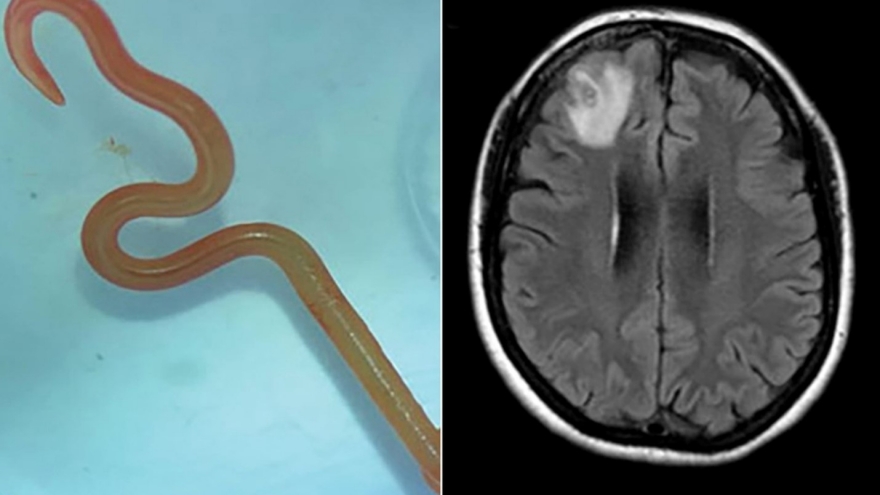

Đau đầu, nóng rát chân dai dẳng, cô gái tá hỏa phát hiện giun "làm tổ" trong não

VOV.VN - Nhập viện vì thường xuyên thấy đau đầu và nóng rát ở chân rồi lan lên khắp cơ thể sau chuyến du lịch Thái Lan, người phụ nữ tá hỏa khi phát hiện giun ký sinh trong não.